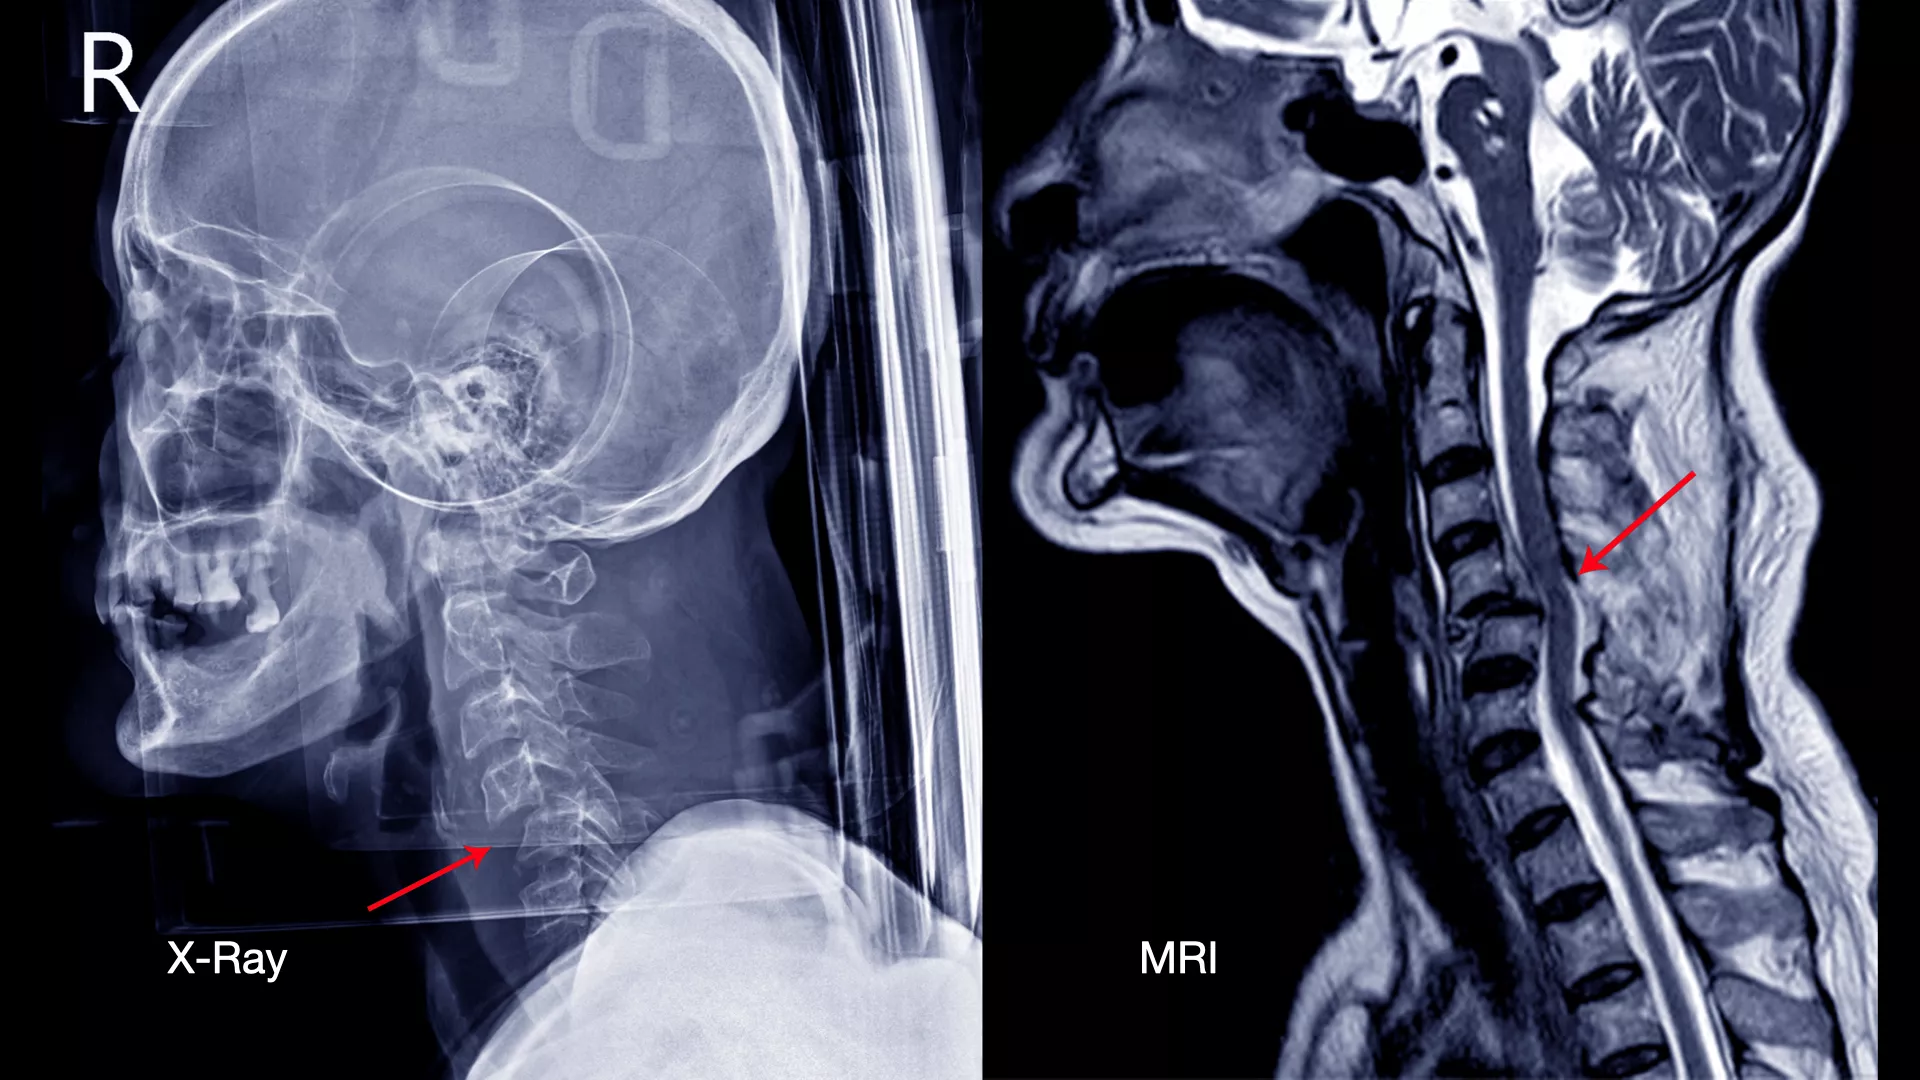

X-ray มาแล้วทำไมต้องตรวจ MRI อีก?

การตรวจด้วย X-ray ทั้ง 4 ท่าจะช่วยให้แพทย์ประเมินภาพรวมของโครงสร้างกระดูกได้อย่างละเอียด แต่ X-ray ไม่สามารถแสดงภาพของเนื้อเยื่ออ่อน (Soft Tissue) เช่น หมอนรองกระดูก เส้นประสาท และไขสันหลัง ได้อย่างชัดเจน

ดังนั้น การตรวจด้วย MRI จึงเข้ามาเติมเต็มในจุดนี้ โดยจะะให้ภาพที่มีความละเอียดสูงและสามารถเห็นรายละเอียดของเนื้อเยื่ออ่อนและลักษณะของรอยโรคได้อย่างชัดเจน ทำให้แพทย์สามารถ

การตรวจทั้ง X-ray และ MRI ร่วมกันจึงเป็นการผสมผสานที่สมบูรณ์แบบ เพื่อให้แพทย์ได้ข้อมูลที่ครอบคลุม ครบถ้วนและแม่นยำที่สุด สำหรับการวินิจฉัยและวางแผนการรักษาที่เหมาะสมสำหรับผู้ป่วยแต่ละราย